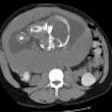

MRI may catch endometrial cysts that morph into ovarian tumors